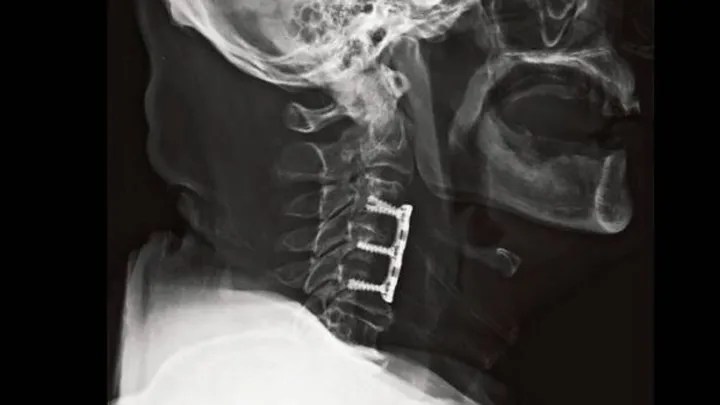

There are various types of cervical spine surgeries, depending on the nature of the condition. Anterior cervical discectomy and fusion (ACDF) is one of the most common procedures, where a herniated or damaged disc is removed, and the two vertebrae are fused to provide stability. Another procedure, cervical artificial disc replacement, involves removing the damaged disc and replacing it with a synthetic one to maintain motion in the neck. In cases of spinal stenosis or nerve compression, laminectomy may be performed to remove part of the vertebrae, relieving pressure on the spinal cord and nerves.

Modern cervical spine surgery often employs minimally invasive techniques that reduce the size of incisions, shorten recovery times, and minimize muscle damage. Surgeons may use advanced imaging technologies such as X-rays, MRI, and CT scans to guide the surgery precisely. Robotic-assisted surgery is also becoming more prevalent, offering enhanced precision and reducing the risk of complications during the procedure.